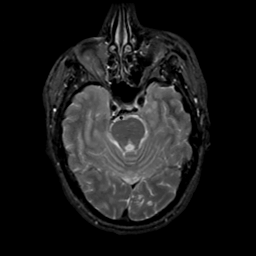

MR Study #20 October 6, 1991 -- Slice #16

[Home][Help][Clinical][Tour 1][Tour 2] Slice 16